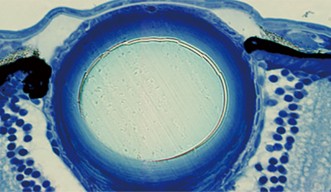

A mutated eye offers a glimpse of a key protein for preventing cancer

Researchers have showcased the central role of a specific protein for stopping cell death and regulating the cell cycle.